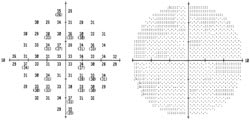

Figure 6. Humphrey VF central -10 (pre- and

8 months-post laser treatment). No worsening of relative or absolute scotomata is

noted. Top – prelaser with CSME; Bottom – after both subthreshold micropulse

diode laser treatments, resolved CSME. |

Complications due to thermal damage to the retina and/or choroid (eg, symptomatic paracentral scotomata, choroidal neovascularization) are minimized with laser pulses of very short duration that affect the RPE alone with little effect on the photoreceptors or choriocapillaris.10,11 Complications such as foveal distortion, accidental foveal burns, subretinal fibrosis, decreased contrast sensitivity, blood vessel perforation, and chorioretinal anastomosis correlate directly with the energy delivered per laser spot. Use of subthreshold micropulse laser should minimize these undesired effects. In our patient, no new relative or absolute scotomata were noted on Humphrey visual field central -10 (Figure 6) or with SLO microperimetry (Figure 7).